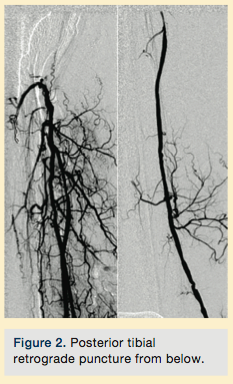

Peripheral angiography showed total occlusion of the right distal superficial femoral artery extending into the popliteal artery and into the trifurcation, with reconstitution of a peroneal and a posterior tibial. We attempted to obtain antegrade access to the lesions of the right infra-popliteal vessels (Figure 1). After failing to cross the lesion, we obtained retrograde access, puncturing from below the lesion through the posterior tibial artery near the ankle joint (Figure 2). Access was obtained and the lesion below the knee was crossed (Figure 3). Following this, the V-18 control wire (Boston Scientific) was snared from above, a CXI support catheter (CSI) was backloaded over the wire, and an antegrade Viperwire (CSI) was then placed, with removal of the retrograde sheath and wire. Atherectomy was performed with the 1.5mm Stealth 360° orbital atherectomy device (CSI) followed by balloon angioplasty with Cook, Sterling (Boston Scientific), and Chocolate (Cordis) balloon catheters. After angioplasty, significant improvement in luminal gain was noted at the expense of a dissection (Figure 4). We chose to place a Zilver PTX drug-eluting stent (Cook) within the distal superficial femoral and popliteal artery segment (Figure 5). After the procedure, the patient’s wounds completely healed. An angiogram 3 months later was performed, showing the vessels to be widely patent (Figure 6). The patient sent us a video of himself finally walking, and without pain (Video 1; online).